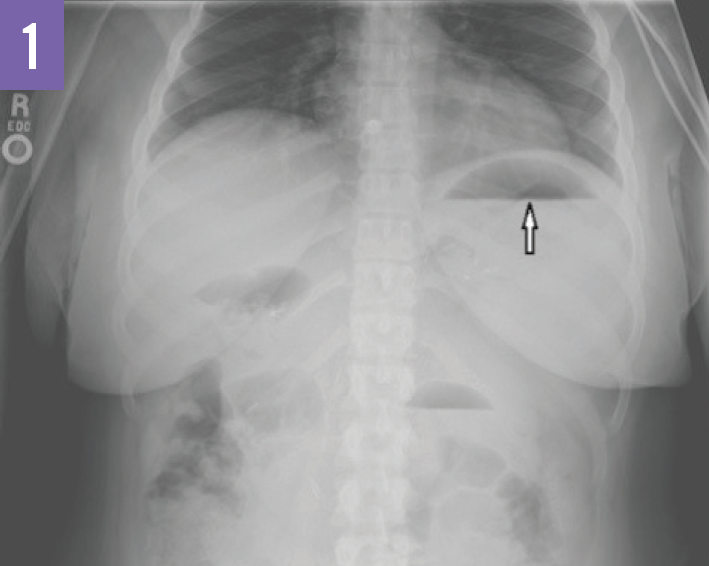

Laparoscopic gastric bypass LGBP internal hernia, plain Xray Post Gastric Bypass Internal Hernia Radiology to evaluate the accuracy of computed tomography (ct) for diagnosis of internal hernia (ih) in patients who have. At the defect in the transverse mesocolon through which. understanding the rygb surgical approach and its appearance at postsurgical ct, as well as the types of postoperative internal hernia and their common. internal hernia, the movement of bowel into. Post Gastric Bypass Internal Hernia Radiology.